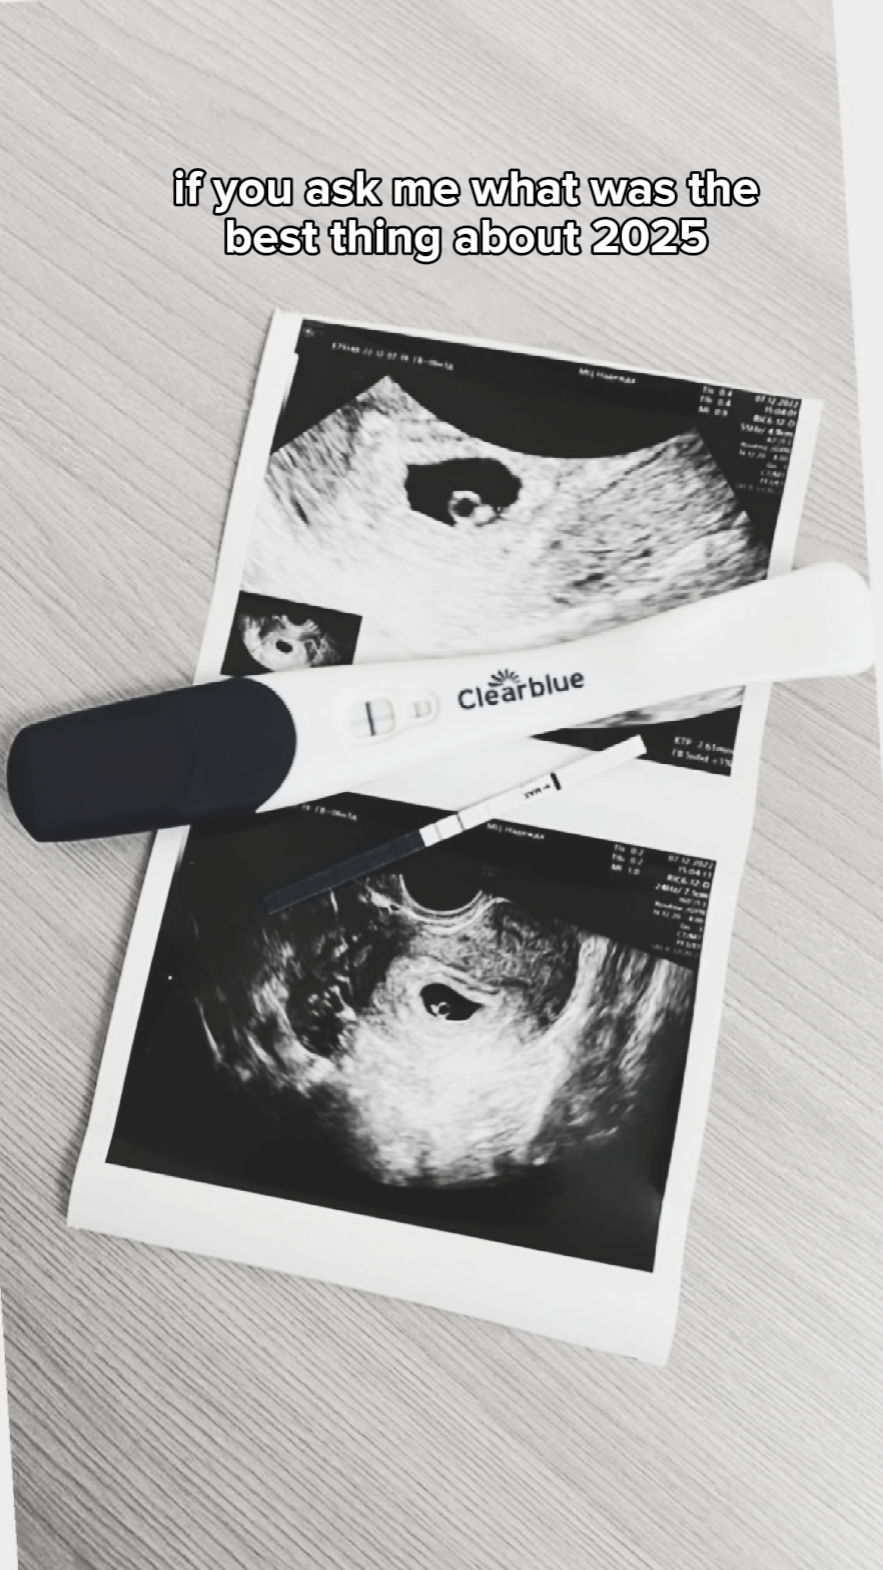

2025 best thing

#pregnancy#parents#baby#2025recap#thankyou2025